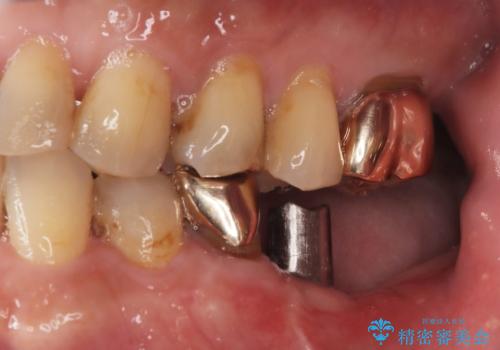

- 「奥歯の銀歯が取れた」を主訴に来院された患者さんです。

診査診断を行った結果、歯が折れた位置が深く、虫歯にもなっていたため抜歯後、インプラントで治療を行いました。

残根状態の歯を抜歯後、抜歯窩の治癒を待ちインプラントを埋入しています。